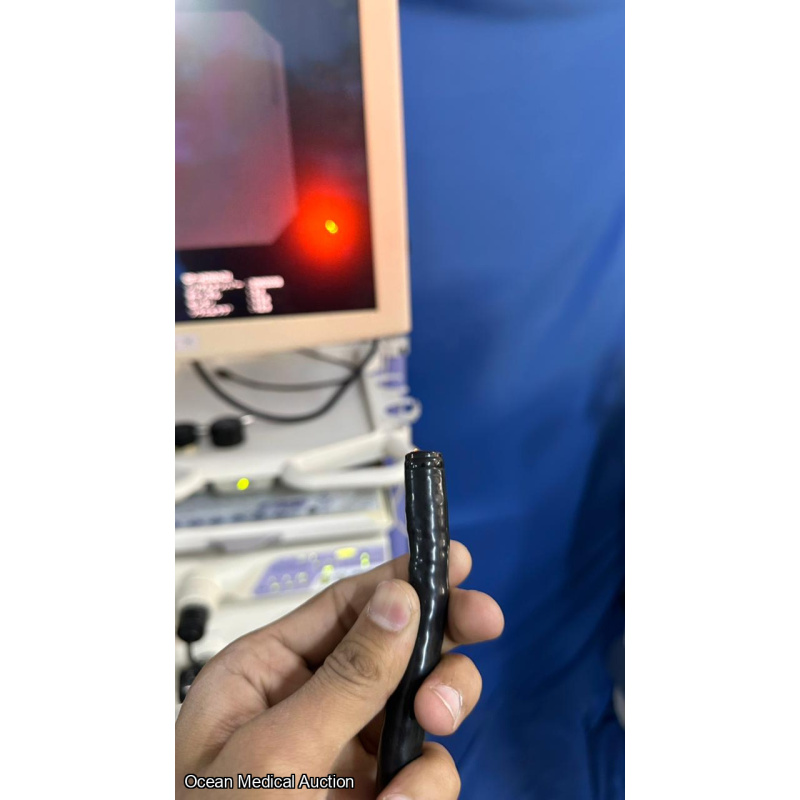

OLYMPUS CF-H260AZI SN.2902038 AND IT IS IN WORKING CONDITION